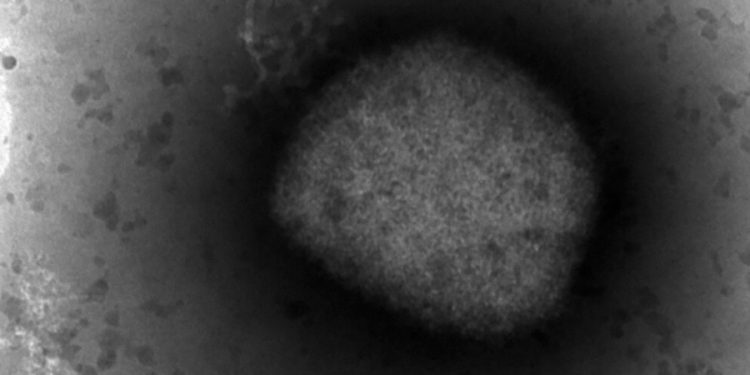

(NewsNation) — The Centers for Disease Control and Prevention (CDC) elevated their travel advisory for monkeypox after more cases were confirmed around the world.

Symptoms of monkeypox include fever, swollen lymph nodes and a distinctive rash.